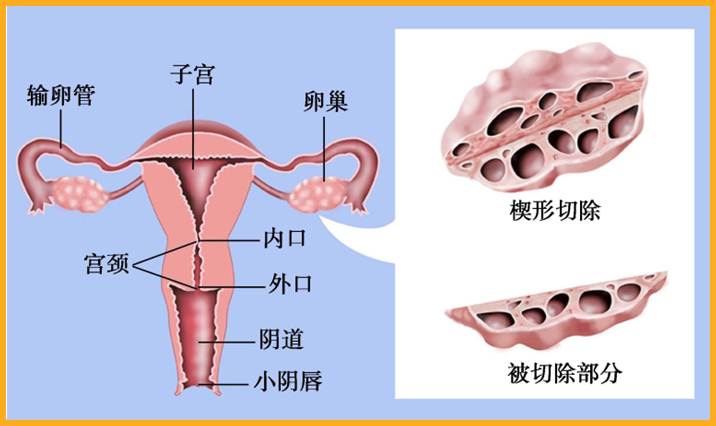

(2)卵巢楔形切除术:将双侧卵巢各楔形切除1/3可降低雄激素水平,减轻多毛症状,提高妊娠率。术后卵果周国粘连发生率较高,临床已不常用。